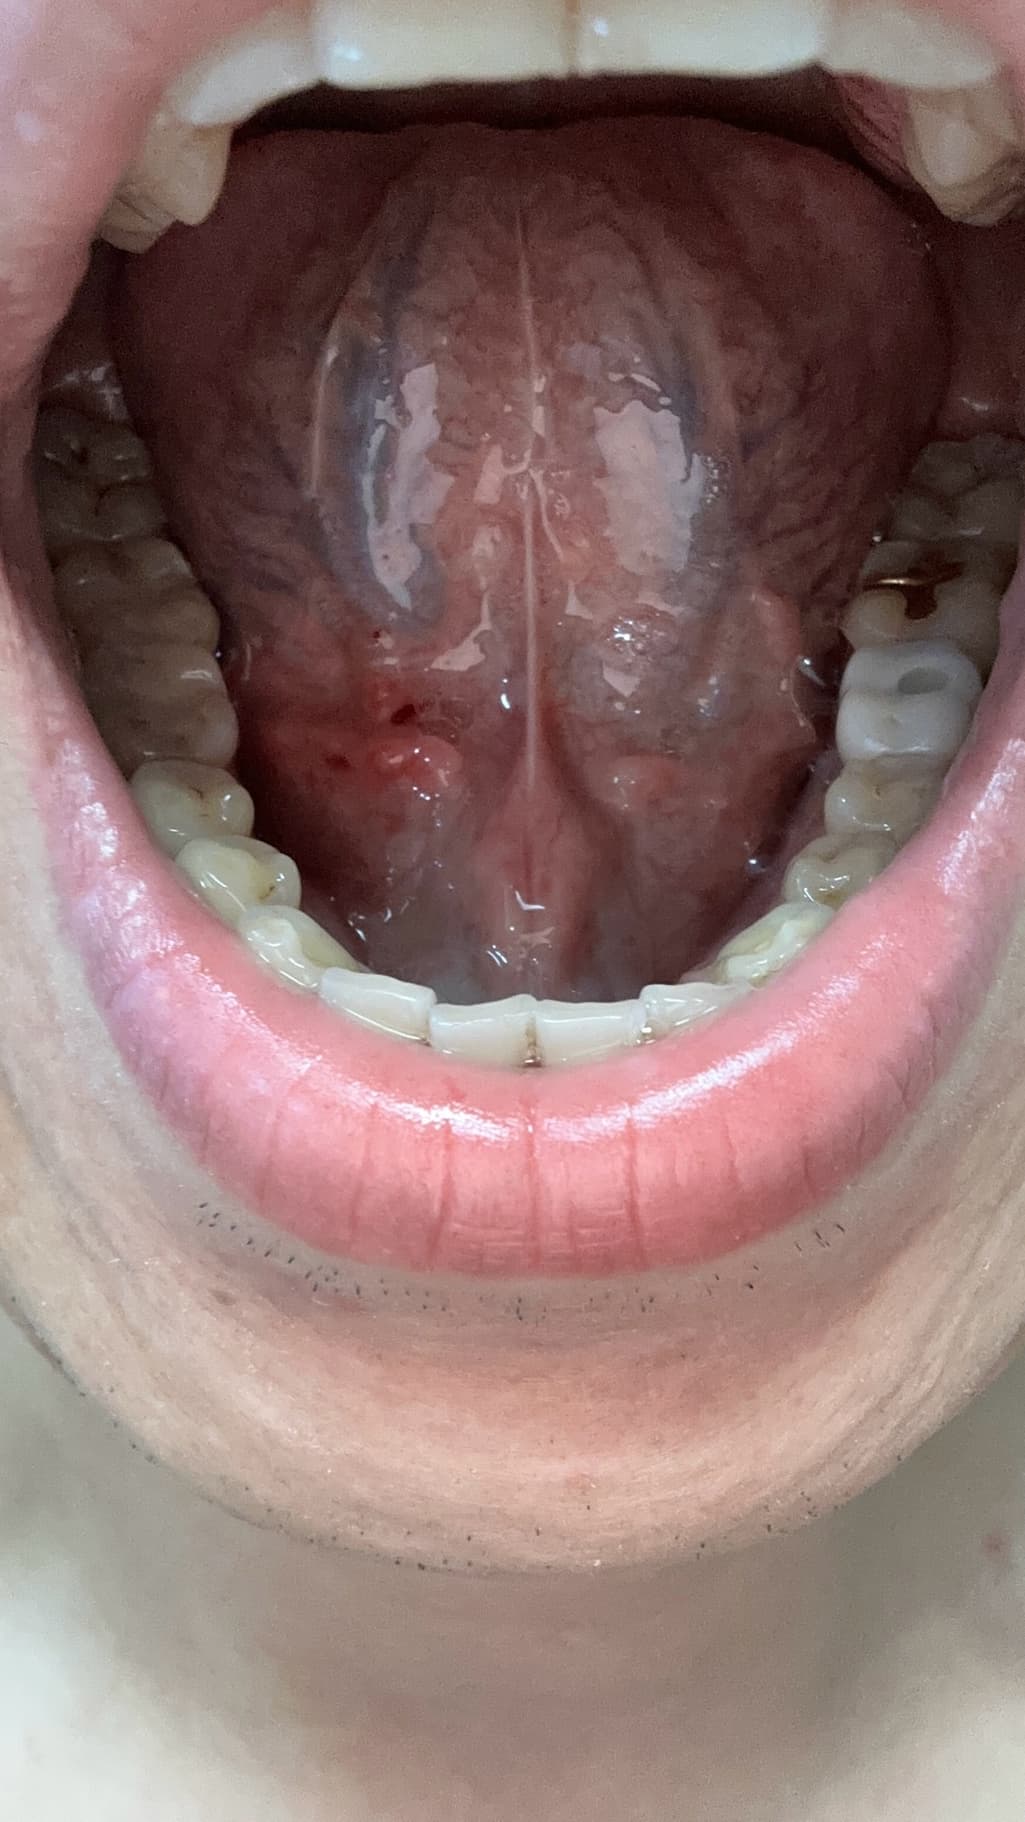

양치하다가 칫솔로 눌렀는데 피나는거처럼 됬어요

빨갛게 된부분이 있는것같고 그래서 이거 병원가봐야되는지 그냥 냅둬도 괜찮음지 궁금해요 어떻게하는게 좋을까요?? 병원은 무슨과인가요?

양치 중 칫솔로 인해 잇몸이 붉어지고 피가 나는 것은 잇몸 염증의 초기 증상일 수 있습니다. 칫솔질 시 잇몸에 과도한 힘이 가해지거나, 치석이나 치태가 쌓여 잇몸이 자극받았을 가능성이 있습니다. 우선 2~3일 정도는 부드러운 칫솔모를 사용하여 잇몸에 자극을 최소화하고, 치실이나 치간칫솔을 사용하여 꼼꼼하게 치아 사이를 청결하게 관리해주세요.

만약 며칠 후에도 증상이 호전되지 않거나, 붓기나 통증이 심해진다면 치과에 방문하여 정확한 진단을 받아보는 것이 좋습니다. 치과에서는 잇몸 상태를 확인하고 필요한 경우 스케일링이나 다른 치료를 통해 잇몸 건강을 회복할 수 있습니다.